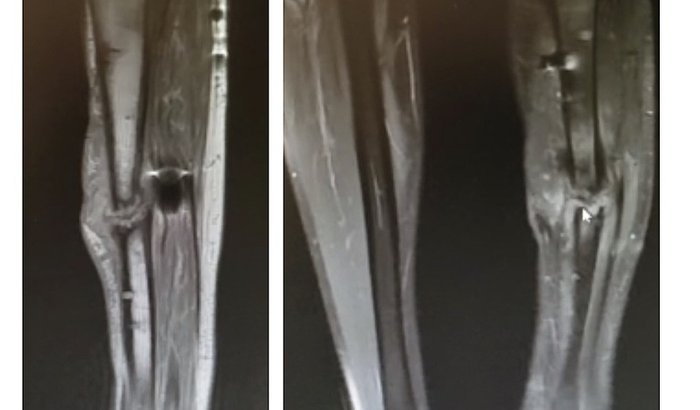

Olá, Meu nome é Thiago Merízio, venho por meio desta mensagem pedir a sua ajuda.  Em abril de 2019 sofri uma acidente que acarretou na fratura exposta da tíbia esquerda.  Como não tenho plano de saúde, penei por meses através do SUS até passar por uma cirurgia definitiva e instalar o Ilizarov (gaiola) na perna.  Após meses de convivência e dor, em janeiro deste ano pude retirar o Ilizarov, porém após alguns dias minha perna voltou a fraturar... no decorrer da investigação médica e após a realização de exames foi verificado que uma infecção no osso que já se extende por 16cm.  A melhor opção de cirurgia é a remoção da parte infeccionada do osso, realizar enxerto ósseo e fixar novamente o Ilizarov (gaiola) na perna esquerda. Essa cirurgia não é oferecida pelo SUS em tempo hábil , onde deverei travar uma batalha judicial para conseguir a realização e infelizmente estou em uma corrida contra o tempo devido à gravidade da lesão.  Mediante isso tudo, venho pedir sua ajuda com qualquer quantia.  Agradeço desde já a sua atenção e que Deus lhe pague.